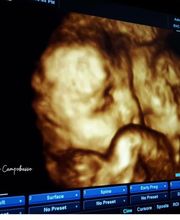

OstetriciaGalleria